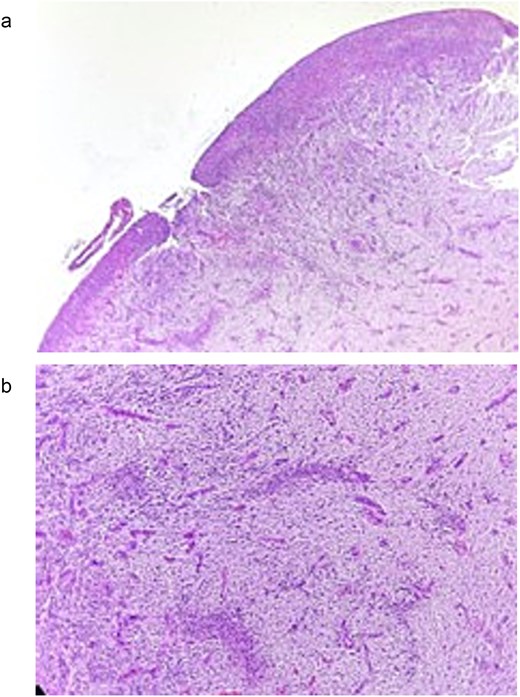

The definitive diagnosis was a PG. Histopathological analysis revealed proliferation of granulation tissue consisting of numerous lymphatic and vascular spaces of different sizes, some congestive, accompanied by severe diffuse chronic inflammatory infiltrate composed of plasma cells, lymphocytes, and histiocytes. The stroma showed abundant collagen fibers arranged loosely and irregularly. An ulcer with loss of epithelial continuity and eosinophilic material compatible with fibrin was also observed (Fig. 3a and b). Histological micro-section stained with hematoxylin and eosin (H&E).

(a) Histological micro-section stained with H&E, showing loss of epithelial continuity and the presence of eosinophilic material consistent with fibrin corresponding to an ulcer. (b) H&E-stained histological micro-section showing granulation tissue consisting of lymphatic and vascular spaces of varying sizes, severe diffuse chronic inflammatory infiltrate, in a stroma of abundant collagen fibers arranged in a loose and irregular manner.